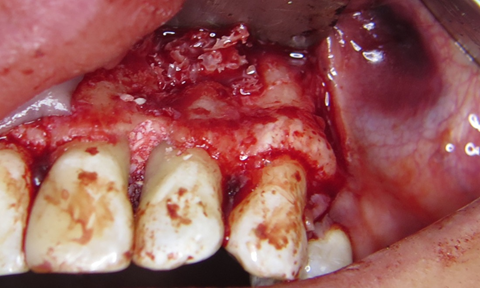

Етап 2. Під інфільтраційною анестезією проведено формування повного клаптя, сформовано доступ до ділянки кістки, проекційно співставлений з периапікальним кістковим дефектом. (фото 4)

За допомогою п’єзохірургічної кулеподібної насадки (СЕ 1, Piezotome Solo (Satelec, Aсteon)) сформовано доступ до периапікального дефекту. (фото 5)